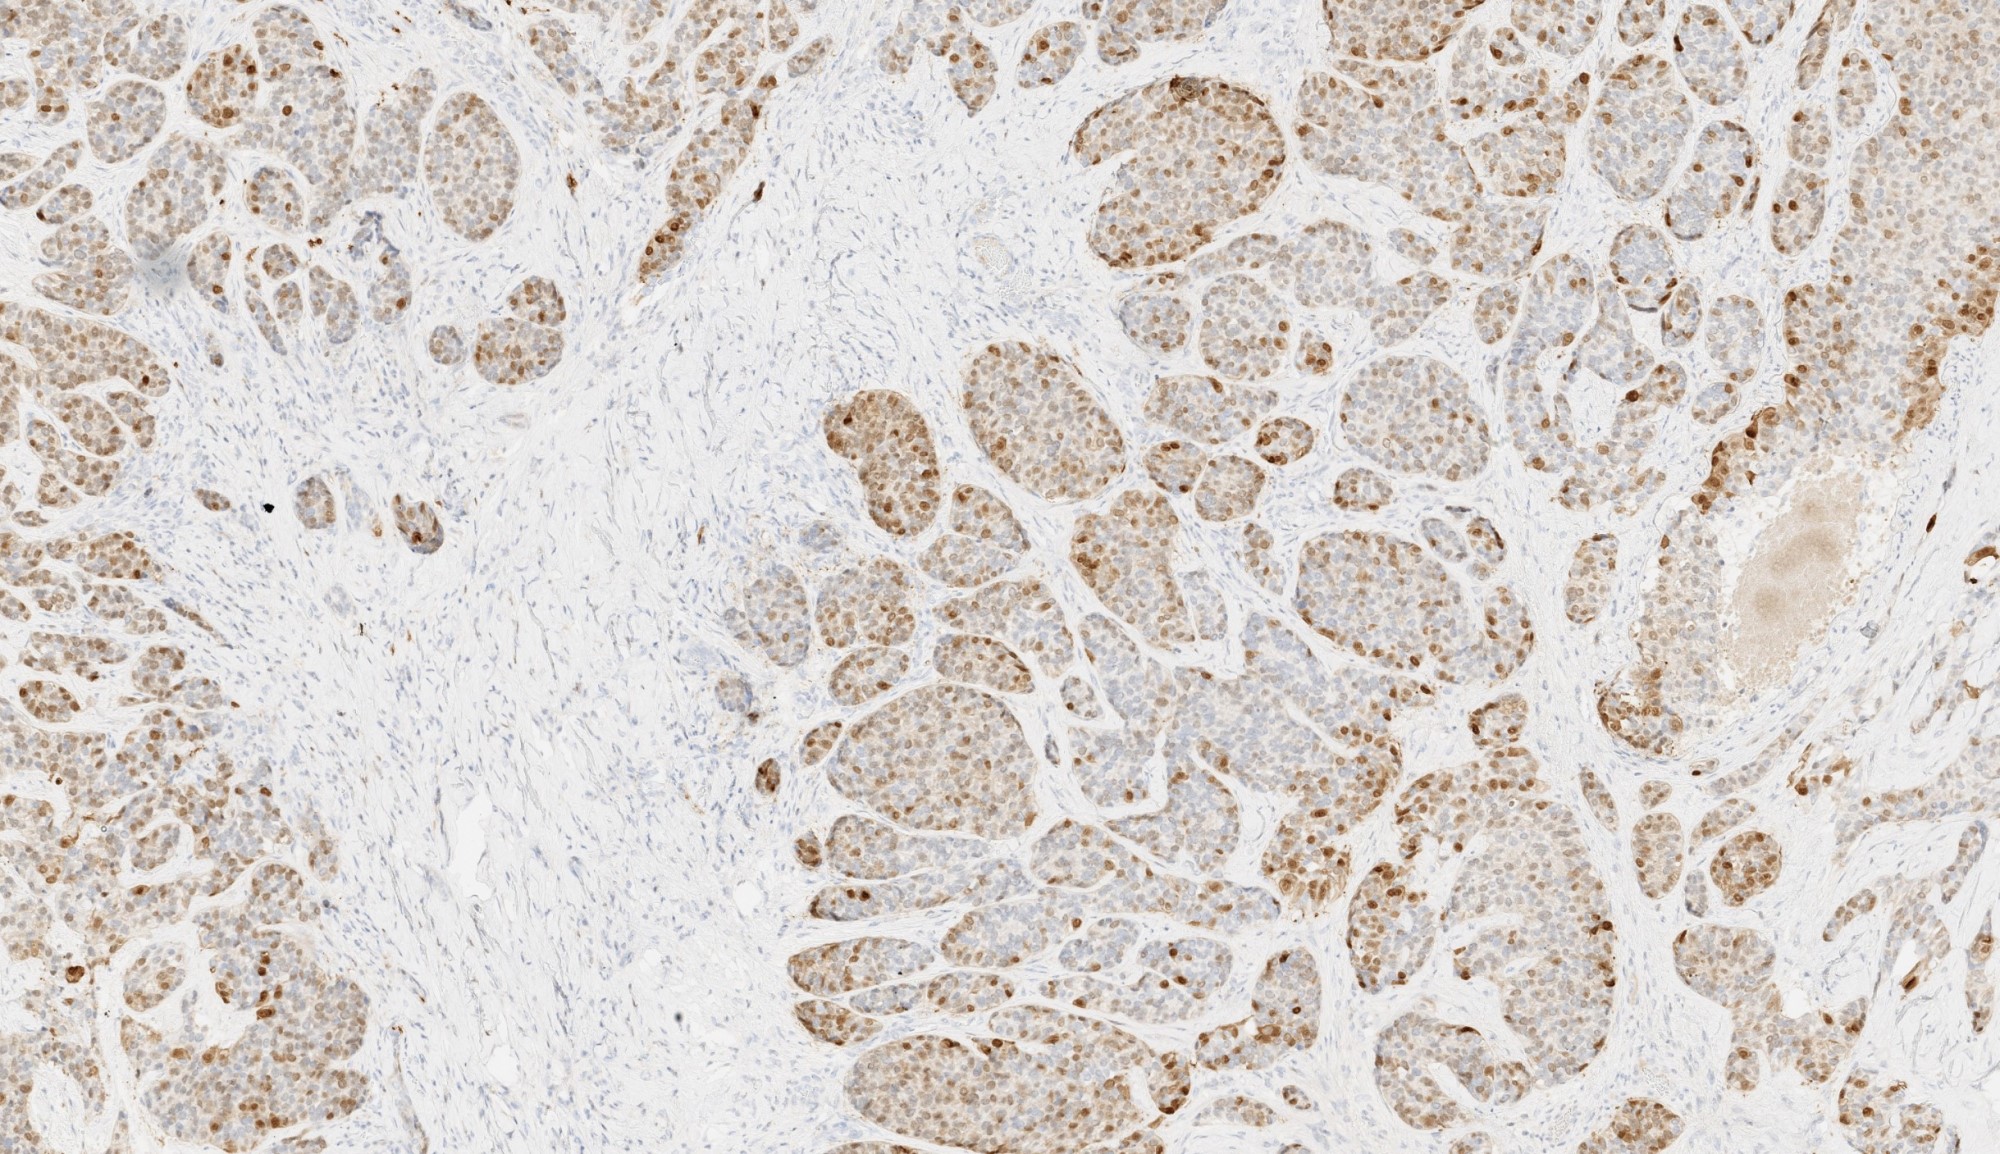

Microscopic (histologic) images

Contributed by Abeer Salama, M.D. and Bin Xu, M.D., Ph.D.

Positive stains

- Comment: The tumor shows a mitotic index of 8 per 10 high power fields. Tumor necrosis is noted. Immunohistochemistry studies show that the tumor is positive for S100, calponin and CAM5.2, whereas negative for HMB45. The morphologic and immunohistochemical features are most consistent with myoepithelial carcinoma.

B. The low power H&E clearly shows invasion, which supports a diagnosis of carcinoma and excludes benign entities, such as pleomorphic adenoma. At high power, the tumor contains one type of tumor cells, which exclude all carcinoma with biphasic patterns (e.g. adenoid cystic carcinoma). The immunohistochemical profile is consistent with myoepithelial phenotype. Therefore, the correct diagnosis is myoepithelial carcinoma.